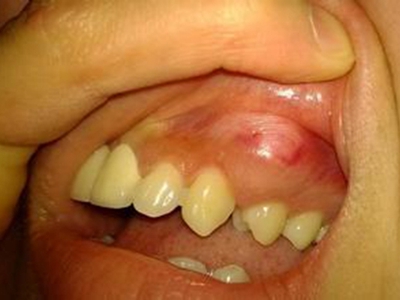

牙龈瘤是指发生在龈乳头部位的炎症反应性瘤样增生物,好发于女性,前磨牙区最为常见。牙龈瘤来源于牙周膜及牙龈的结缔组织,因其无肿瘤的生物学特征和结构,故非真性肿瘤,但切除后易复发,因此切除务必彻底,必要时拔除相关牙齿。

牙龈瘤多发于女性,以青年及中年人为常见,多发生于牙龈乳头部,位于唇、颊侧者较舌、腭侧者多,最常见的部位是前磨牙区。肿块较局限,呈圆形或椭圆形,有时呈分叶状,大小不一,直径由几毫米至数厘米。

肿块有的有蒂,如息肉状;有的无蒂,基底宽广,生长较慢,但在女性妊娠期间可能迅速增大。较大的肿块可以遮盖一部分牙及牙槽突,表面可见牙压痕,易被咬伤而发生溃疡,伴发感染。随着肿块的增长,牙槽骨壁逐渐被破坏,牙可能发生松动、移位。